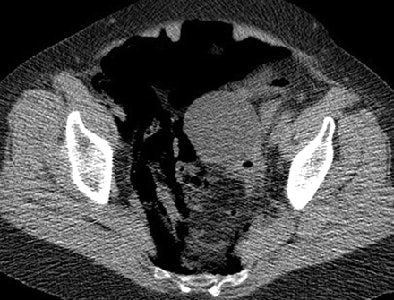

The second patient with perforation was a 70-year-old woman who had undergone screening colonoscopy. Acute angulation of the sigmoid colon prevented the colonoscope from being advanced more than 25 cm, and after five minutes of unsuccessful maneuvering it was removed. The patient had mild tenderness of the abdomen but no peritonism. She was admitted overnight and treated with antibiotics and IV fluids.

Overnight she developed worsening pain and a 38° C fever. "A diatrizoate meglumine and diatrizoate sodium solution enema examination the following morning showed no evidence of leak," they wrote. Symptoms resolved within 48 hours, and the patient was discharged from the hospital three days later with no further complications.

| Seventy-year-old woman who has undergone incomplete colonoscopy. Above and below: Axial CT scans of abdomen obtained before CT colonography show extensive retroperitoneal gas secondary to colonic perforation. Bottom image: Scout view from same examination shows extensive retroperitoneal air. All images courtesy of the American Roentgen Ray Society. Source: Hough DM, Kuntz MA, Fidler JL, et al. Detection of occult colonic perforation before CT colonography after incomplete colonoscopy: perforation rate and use of a low-dose diagnostic scan before CO2 insufflation. AJR. 2008;191:1077-1081. |